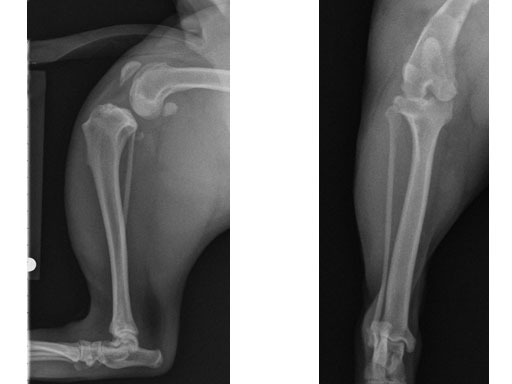

Case 1: Two-year-old Labrador Retriever

2-years-old Labrador Retriever, 30 kg, female. Chronic lameness in both hind limbs, chronic bilateral cranial cruciate ligament tears, with subsequent stifle joint instability and degenerative joint disease. At that time, she was more clinically lame on the left hind limb, and a surgical correction was subsequently performed on this limb. X-rays of the stifle joint revealed the degenerative joint changes and an effusion; the tibial plateau slope was 20. In addition, the x-rays confirmed that there was a slight amount of tibial torsion that also was observed clinically, accounting for a slight internal rotation of the distal limb. Radiographically, this could be assessed by a 4 mm shift of the normal point of intersection of the medial aspect of the calcaneus with the deepest point of the talar sulcus.